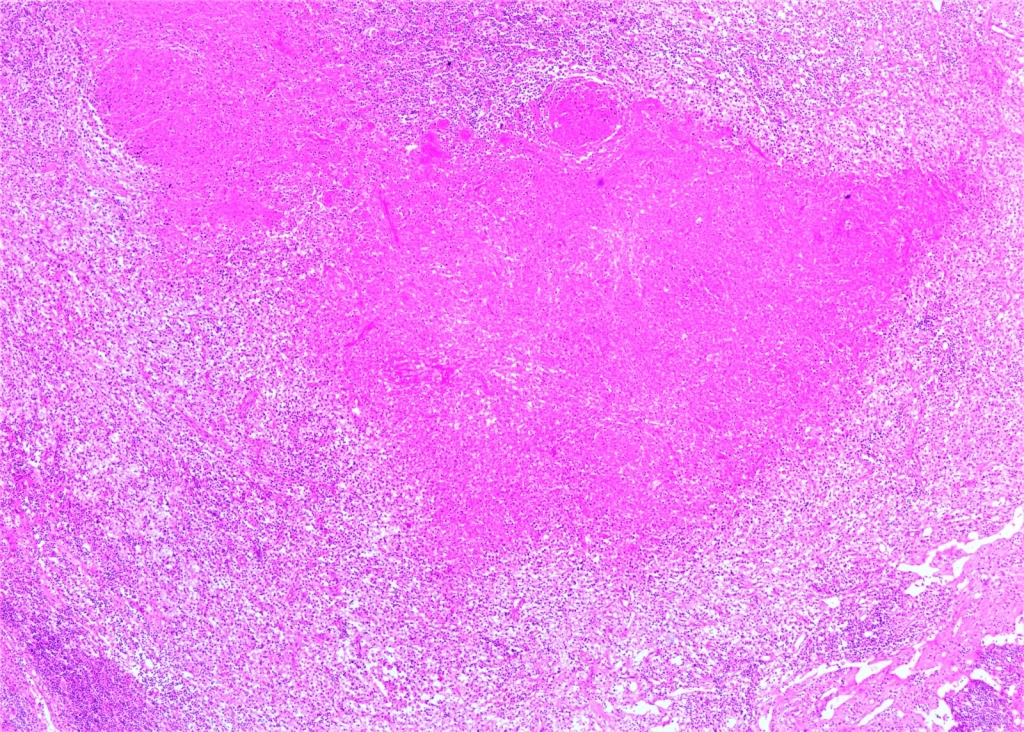

AbstractKikuchi–Fujimoto Disease (KFD) is a rare condition. Due to its rarity, accurate diagnosis is often delayed, and patients may receive incorrect diagnoses and treatments. Moreover, this disease may precede the development of various systemic illnesses. Early diagnosis allows for a more controlled disease course. In this study, we present two patients who were admitted to our clinic with complaints of cervical swelling and were diagnosed with KFD based on excisional biopsy findings.IntroductionKikuchi–Fujimoto Disease (KFD), also known as histiocytic necrotizing lymphadenitis, was first described in Japan in 1972 by Kikuchi and Fujimoto. This rare disease is typically a self-limiting inflammatory condition. However, a few reports in the literature have documented fatal outcomes. Although KFD is thought to predominantly affect children and young adults of Asian descent, cases have been reported in individuals of various ages and ethnic backgrounds. KFD usually presents with an acute or subacute clinical course. In addition to systemic symptoms such as fever, fatigue, weight loss, arthralgia, and skin lesions, the disease is characterized by painful, tender, and mobile cervical lymphadenopathy (LAP) [1,2] . Most patients exhibit relative leukocytosis, leukopenia, or neutropenia. Since there is no specific test for the disease, definitive diagnosis is made through histopathological examination of an excisional lymph node biopsy. However, some studies have suggested that fine-needle aspiration biopsy may also be helpful in establishing the diagnosis [3]. In this report, we present two patients who presented to our clinic with complaints of neck swelling and were diagnosed with KFD after thorough evaluation. Through these cases, we aim to raise clinicians’ awareness of this rare condition. Case ReportCASE 1 A 42-year-old male patient presented to our clinic with a one-month history of painful swelling in the neck. On physical examination, a mobile, tender, approximately 3 cm mass was palpated at the left cervical level 2A. Other routine ear, nose, and throat (ENT) examinations were unremarkable. Neck ultrasonography (USG) revealed an asymmetrical lymph node with a thickened cortex measuring 33 × 11 mm, located deep to the left sternocleidomastoid (SCM) muscle near the mandibular angle, and showing central vascularity. Laboratory investigations showed a borderline elevated erythrocyte sedimentation rate (ESR: 22). Other routine blood tests were within normal limits. Viral screenings for Epstein–Barr virus (EBV), Herpes Simplex virus (HSV), and Cytomegalovirus were all negative. An excisional biopsy was planned. The LAP was excised from the left cervical level 2A. Histopathological examination confirmed the diagnosis of KFD. Histopathological evaluation demonstrated extensive geographic necrosis within the lymph node in the absence of neutrophilic infiltration, a characteristic finding of KFD ( Figure 1,2).